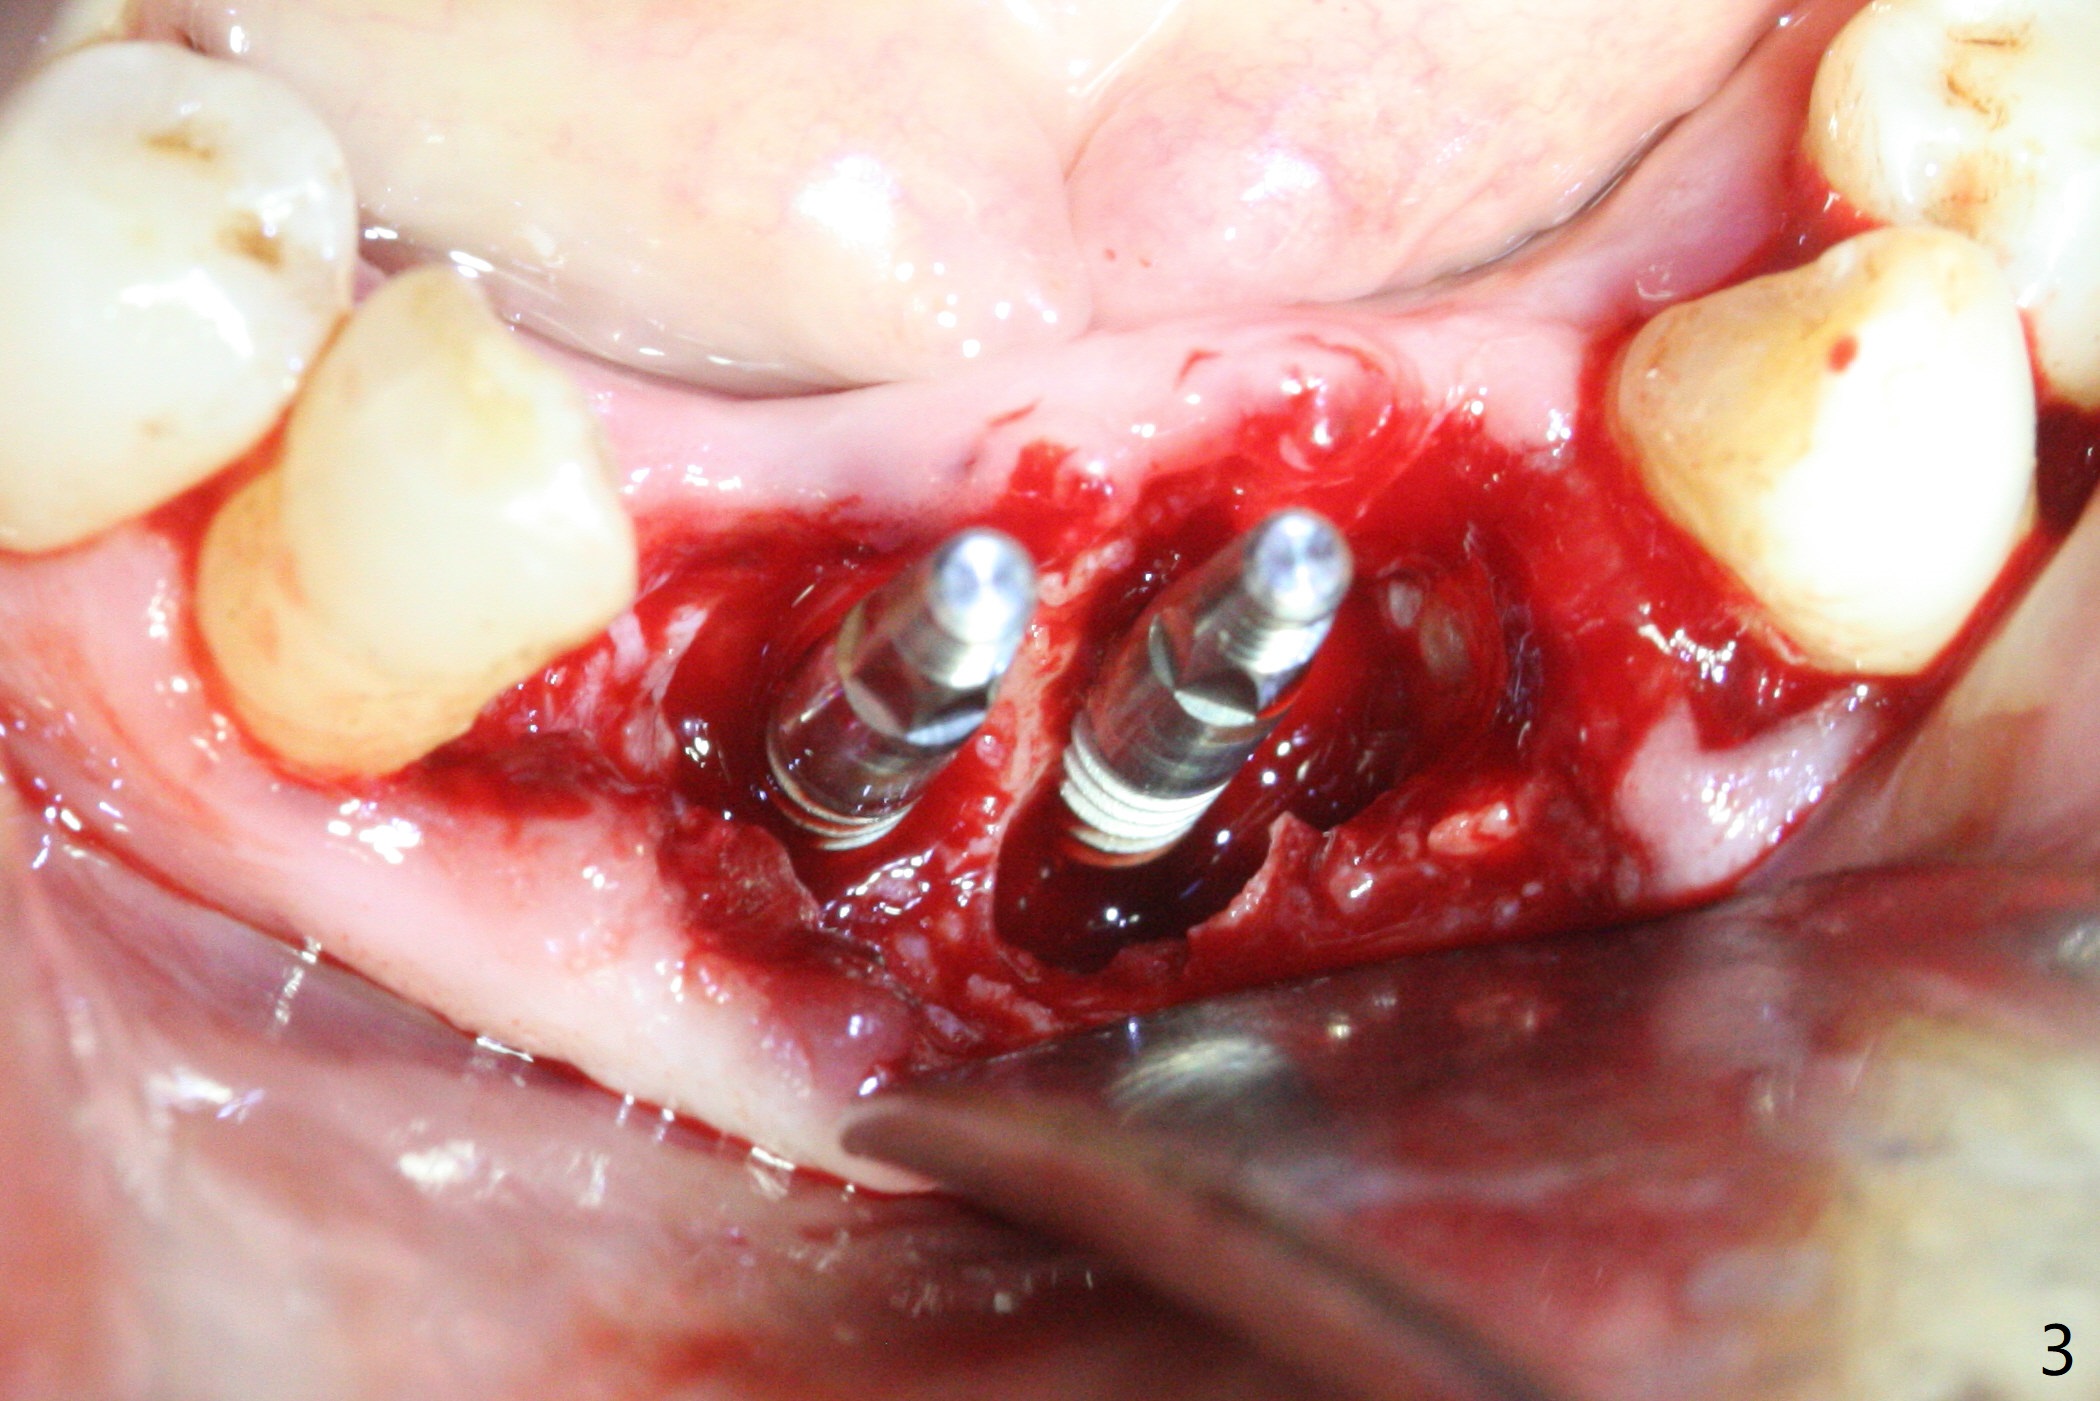

When the patient (smoker) returns for treatment, the apical abscess associated with #25 and 26 reduces with oral Amoxicillin. He agrees with 4 incisor extraction because of 2 apical fistulae (Fig.1 >). Osteotomy starts at the central incisor sockets due to mesial root exposure of the canines (Fig.2 arrowheads) and buccal alveolar bone fracture between #23 and 24 (Fig.7). Two of 3x14(4) mm 1-piece implants are placed with ~ 2 mm buccal gap (Fig.3). After Vanilla graft is placed in the bony defects (Fig.5 *) and Osteogen plug, sutures are placed (Fig.4). The implants are then placed deep to decrease thread exposure (Fig.6). Periodontal dressing is applied instead of provisional. Alveolar bone fracture between #23 and #24 accounts for why an implant is less suitably placed at #24 (Fig.7). Three months postop, composite is added to the pontic areas of the provisional (Fig.8 *). When the provisional is seated, the convex pontics press the used-to-be-flat gingiva (Fig.9 arrows). Thus the concave gingiva forms (Fig.10 *) with corresponding papillae (^). In fact the photos of Fig.8-10 is taken ~3 weeks later. Most of the grafted bone remains in place 3.5 months postop (Fig.11). A piece of floss with 2 knots in one end is placed between the middle units of the final bridge before cementation (Fig.12 (4 months 10 days postop)). In fact removal of residual cement is not so simple. It is tedious (Fig.13,14). An asymptomatic buccal fenetration with implant thread exposure is found 2 months post cementation and persists for another month in spite of advice to reduce smoking (1/2 ppd) and use of water pik (Fig.15). The area will be debrided, followed by bone graft and PRF in a month.